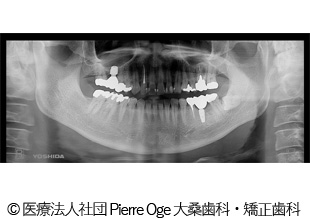

【症例2】左上34、左下5 インプラント治療

- 治療前

- 治療後

- 治療名

- 左上34、左下5 インプラント治療

- 費用

- 1,358,000円(税込)

- 費用の詳細

- 検査代:32,000円(税込)/手術代:690,000円(税込)/補綴代:636,000円(税込)

※当時の金額 - 期間

- 1年1ヵ月

- 通院回数

- 10回

- 性別・年齢

- 40代男性

治療内容

患者様の症状

重度の虫歯。インプラント治療希望でご来院されました。

治療方法

重度の虫歯になった歯を抜き、代わりにインプラントを埋入。骨量が少なかったため同時に人工骨移植。その日に仮歯まで装着。その後、インプラントが安定してから本物の被せ物を入れることで機能面・審美面の回復に繋がりました。

治療結果

重度の虫歯を補うことができ、機能面・審美面の回復に繋がりました。

治療を行う上での注意点(リスク・副作用)

疼痛、腫脹、青アザ、出血、神経麻痺、鼻出血、補綴物の破損、インプラント体の破折、咬合違和感、インプラント周囲炎。